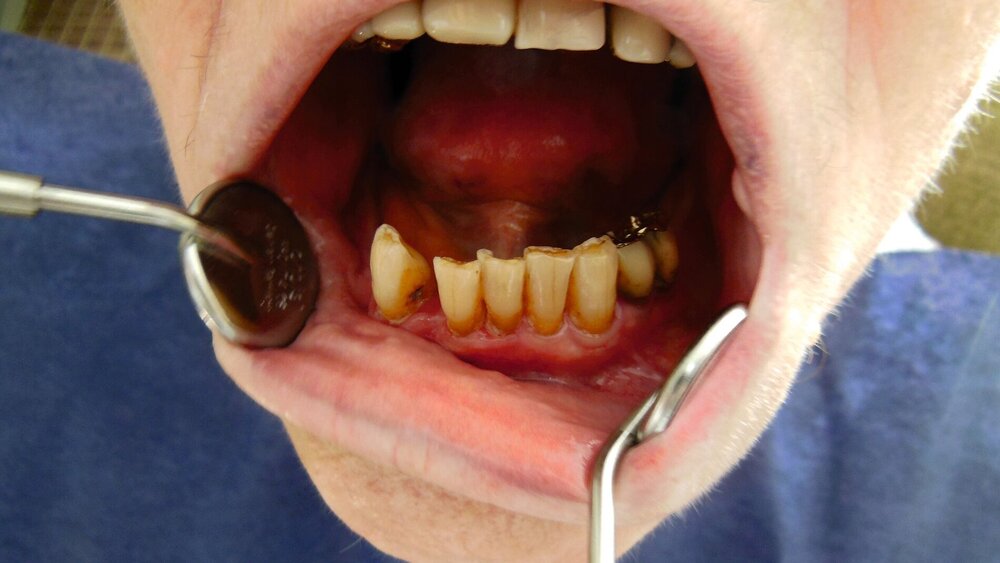

Das Thema Mundgesundheit in der häuslichen Pflege ist für die BZÄK schon länger ein Schwerpunktthema, unterstrich BZÄK-Präsident Prof. Dr. Christoph Benz anlässlich der Ausschreibung des Awards. Aus der Deutschen Mundgesundheitsstudie (DMS V) ging hervor, dass mindestens 30 Prozent der pflegebedürftigen Menschen bei der Mundpflege auf Unterstützung angewiesen sind. Mit Blick auf die Angehörigen sagte Benz: „Manchmal müssen diese sich von heute auf morgen in die Thematik der Pflege eines geliebten Menschen einarbeiten. Dabei bleibt die Mundgesundheit häufig auf der Strecke. Wir wollen mit unserer Initiative das Bewusstsein dafür wecken und gute präventive Ansätze aus der Praxis unterstützen.“

Dr. Burkhard Selent, Director Scientific Affairs bei CP GABA, weist auf den engen Zusammenhang von Mundgesundheit und Allgemeinerkrankungen wie Diabetes oder Herz-Kreislauf-Erkrankungen hin: „Wenn die Mundgesundheit eines Pflegebedürftigen leidet, kann das auch Auswirkungen auf sein Allgemeinbefinden haben, dem gilt es frühzeitig entgegenzuwirken.“